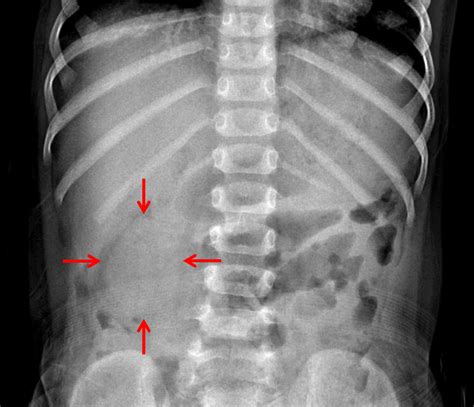

The primary concern when a patient presents with significant abdominal pain is a bowel obstruction. A bowel obstruction is a serious condition where part of the small or large intestine is blocked, preventing the passage of food, gas, and stool. Left untreated, it can lead to bowel perforation or tissue necrosis.

By identifying a nonobstructive bowel gas pattern, physicians can effectively rule out a mechanical blockage as the primary cause of acute, life-threatening symptoms. This allows the medical team to shift their focus toward other potential causes of discomfort, such as:

Feature Nonobstructive Pattern Obstructive Pattern

Gas Distribution Scattered throughout the small and large bowel. Localized to specific, dilated segments.

Bowel Diameter Within normal physiological limits. Significantly dilated (swollen).

Gas-Fluid Levels Minimal or absent. Prominent, indicating trapped air and liquid.

Clinical Implication Usually benign/functional issue. Requires immediate medical intervention.